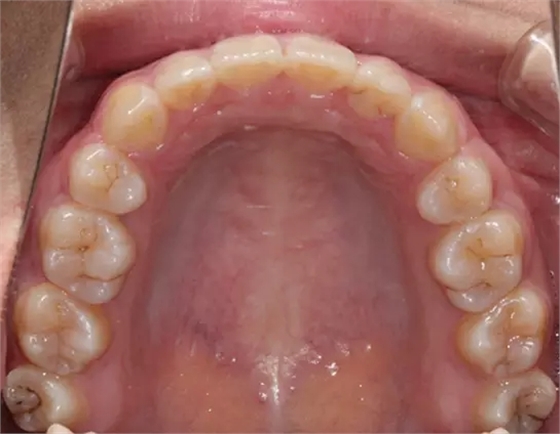

上下牙列擁擠,磨牙尖牙Ⅱ 類關(guān)系,3 度的深覆牙合,上頜中切牙伸長內(nèi)傾拔除上頜雙側(cè)的第一前磨牙,先粘上頜高轉(zhuǎn)矩的自鎖托槽排齊牙列,唇向開展上頜切牙,有一定的覆蓋,粘下頜標準轉(zhuǎn)矩托槽,上頜 1, 2 之間植入種植支抗壓入,同時后牙 5, 6 之間植入種植支抗內(nèi)收前牙,打開咬合關(guān)閉間隙。治療關(guān)鍵:前牙轉(zhuǎn)矩的控制第 1 個月 上頜粘上 Damon Q 高轉(zhuǎn)矩托槽,上 .014 熱激活 NiTi 絲。第 3 個月 上換 .014 x .025 熱激活 NiTi 絲。第 5 個月 上頜基本排齊,覆蓋增大,上換 .017 x .025 NiTi絲,下頜粘托槽,下 .014 熱激活 NiTi 絲。第 7 個月 上 .017 x .025 NiTi 絲加搖椅,下?lián)Q .014 x .025 熱激活 NiTi 絲第 9 個月 上頜換 .019 x .025 NiTi 絲加搖椅,下頜換 .017 x .025 NiTi 絲第 11 個月 下頜換 .019 x .025 加搖椅,上頜 1, 2 之間, 5, 6 之間植入種植釘,下頜出現(xiàn)散隙。第 13 個月 上頜換 .019 x .025ss 加搖椅,前牙種植釘用 Power Chain 壓低前牙(每側(cè) 100g),后牙種植釘關(guān)閉間隙(每側(cè) 150g),下?lián)Q .019 x .025ss,Power Chain 關(guān)閉間隙。第 19 個月 上頜前牙基本壓低到位去除前牙種植釘,繼續(xù)用關(guān)閉間隙,下頜散隙關(guān)閉。

第 22 個月 上頜覆蓋變小,去除 5, 6 之間種植釘,后牙前移關(guān)閉間隙。第 30 個月 患者未配合中線牽引,下中線仍有 1mm 右偏,患者對矯治效果滿意要求拆除,拆除固定矯治器,取模制作壓模保持器。 1.骨性 Ⅱ 類的患者內(nèi)收前牙時需對上頜前牙的轉(zhuǎn)矩進行較好的控制才能獲得良好的面型和唇部形態(tài)。 2.露齦笑的患者治療前要分析其病因是唇、牙齦、牙齒、牙槽骨、上頜骨或多種因素結(jié)合,再制定矯治方案。 3.Ⅱ 類第二分類伴露齦笑的患者的上頜前牙移動軌跡是唇向開展-壓低-整體內(nèi)收。 4.Ⅱ 類第二分類牙齒舌傾比較厲害的情況,上頜中切牙慎用樹脂咬合墊。 5.壓低前牙或控根移動時容易發(fā)生牙根的吸收,需輕力緩慢的移動。